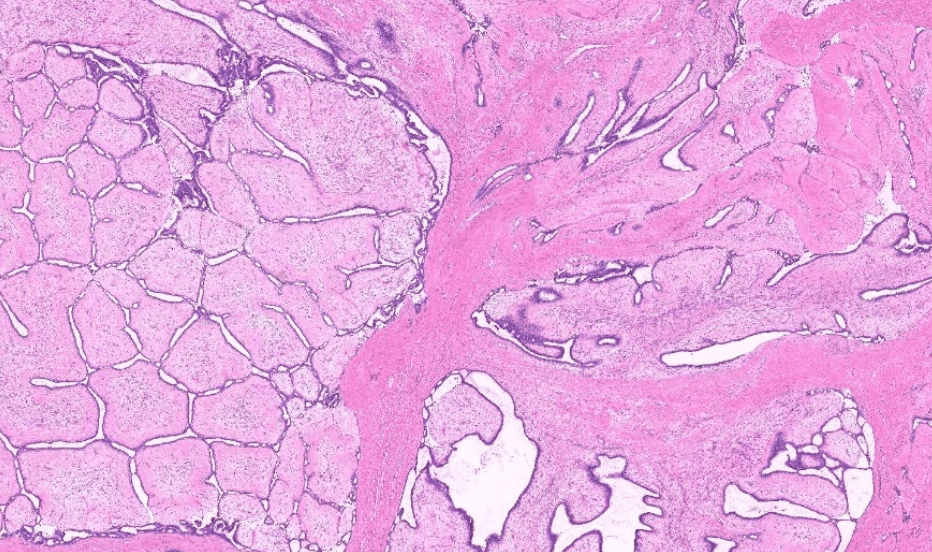

colon cancer